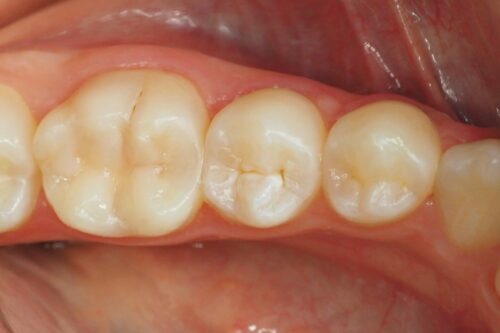

Całkowicie opracowano ubytek, wykonano wytrzymałe i estetyczne wypełnienie kompozytowe będące praktycznie nie do odróżnienia w tkankami własnymi zęba